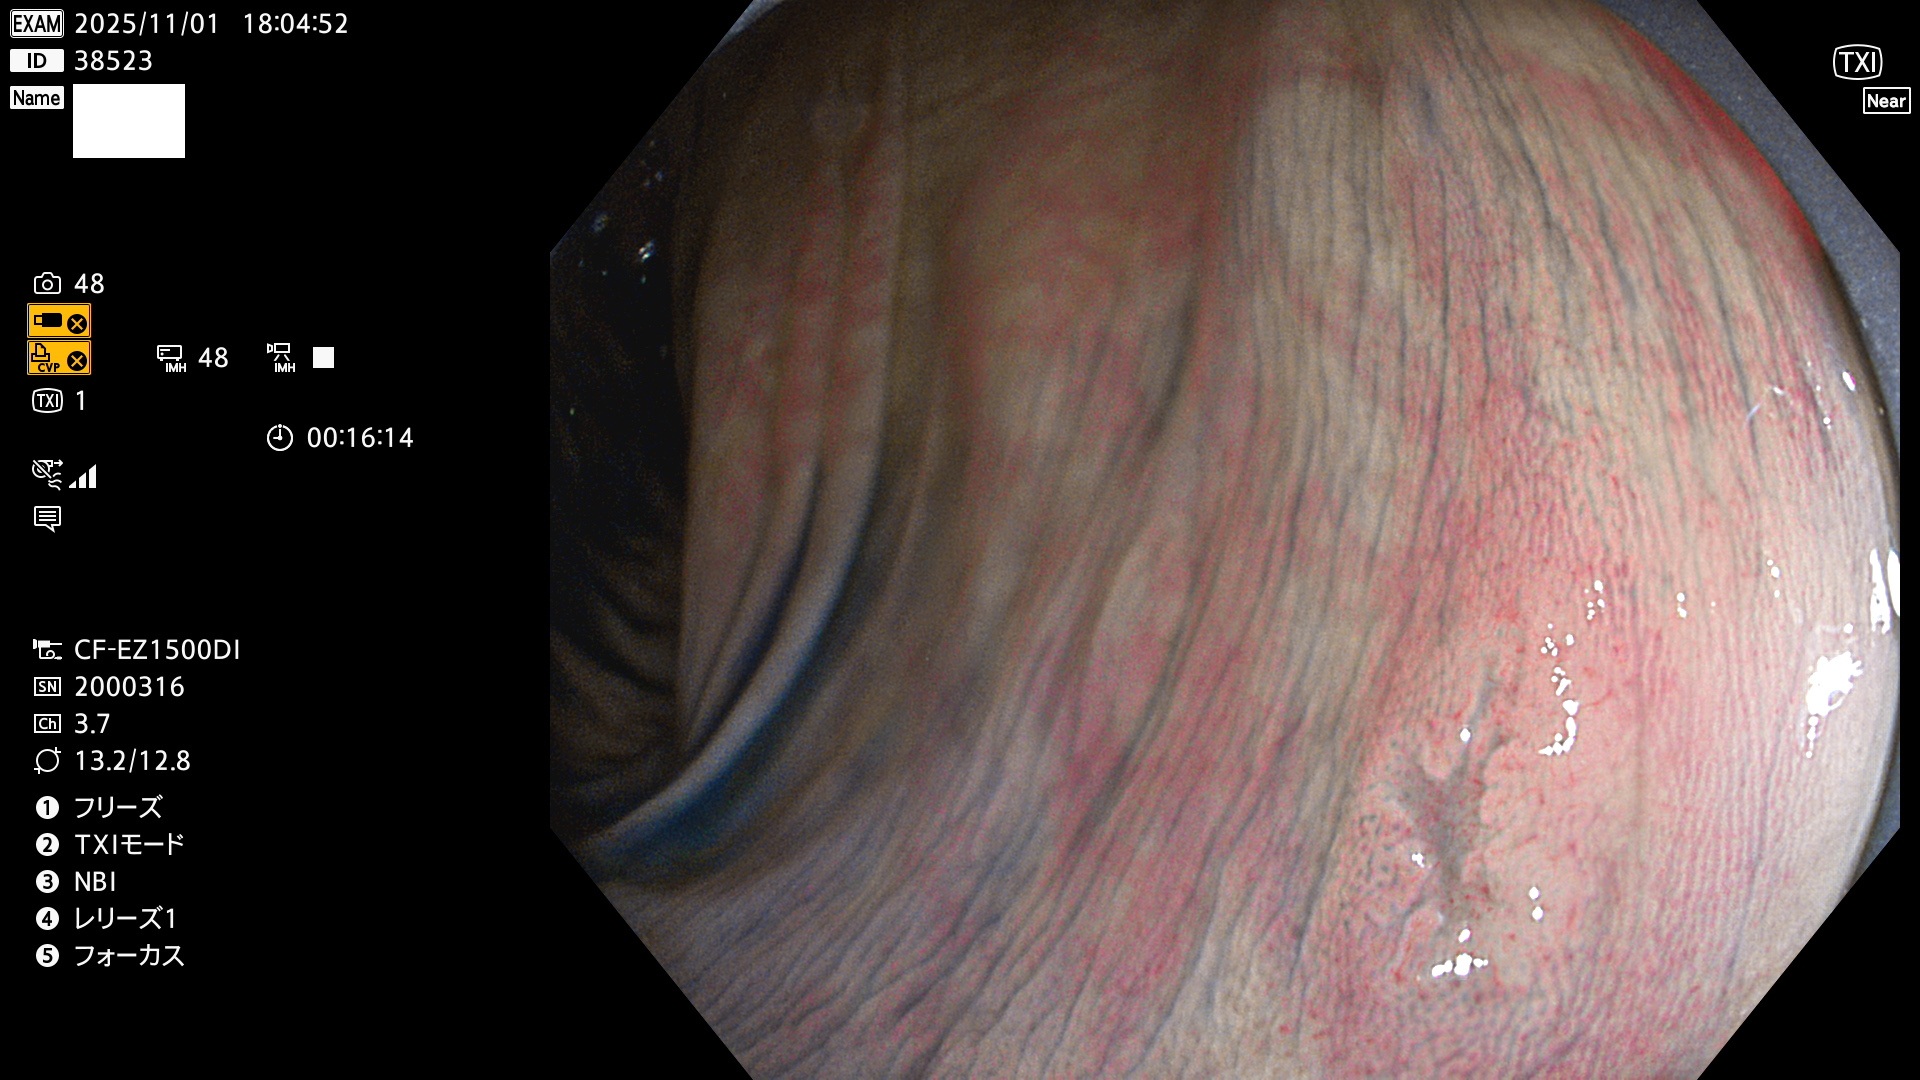

完全に平坦な物をUb、陥凹している物をUcと呼びます。Ubは認識が困難で、Ucはびらん(炎症)と紛らわしいために見落とされやすく、「内視鏡後・大腸癌」の原因になります。

専門的)Uc=De Novo癌? 内視鏡の解像度が低かった時代、このような説もありました。しかし今日の高精度内視鏡では良性の微小なUc型腺腫(APC遺伝子異常の腺腫)が日常的に見つかります。Ucこそが多段階発癌(Adenoma-Carcinoma Sequence)のMain Routeです。

毎週の検査(木・金・土・日)に発見されたUbとUc型・腺腫を、その週の日曜の夜にUPし1週間、提示します。

2025年10月30日〜11月2日の4日間(40件)9個 (Uc_ADR=9個/40人=23%)